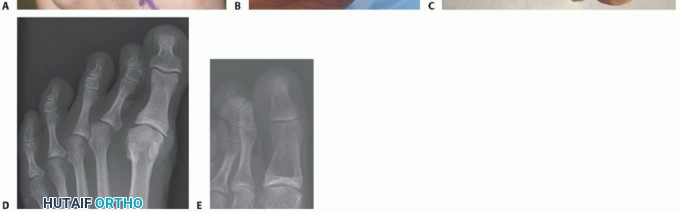

FIG 1 • A. Crossover second toe deformity. B. Congenital crossover of the fifth toe. C. Curly toe deformity. D.*

Isolated MTP angular deformity. E. Clinodactyly.

Crossover second toe deformity (FIG 1A) is characterized by a second toe that lies dorsomedially relative to the hallux.

Isolated MTP angular deformity (FIG 1D) is varus or valgus angulation of the lesser toes occurring solely through the MTP joint. This often occurs in conjunction with great toe varus or valgus deformity.

Clinodactyly (FIG 1E) is varus or valgus deviation of a toe caused by angulation within the phalanx itself. This condition is more commonly seen in the fingers and is often associated with a syndrome (eg, symphalangism) or chromosomal disorder.